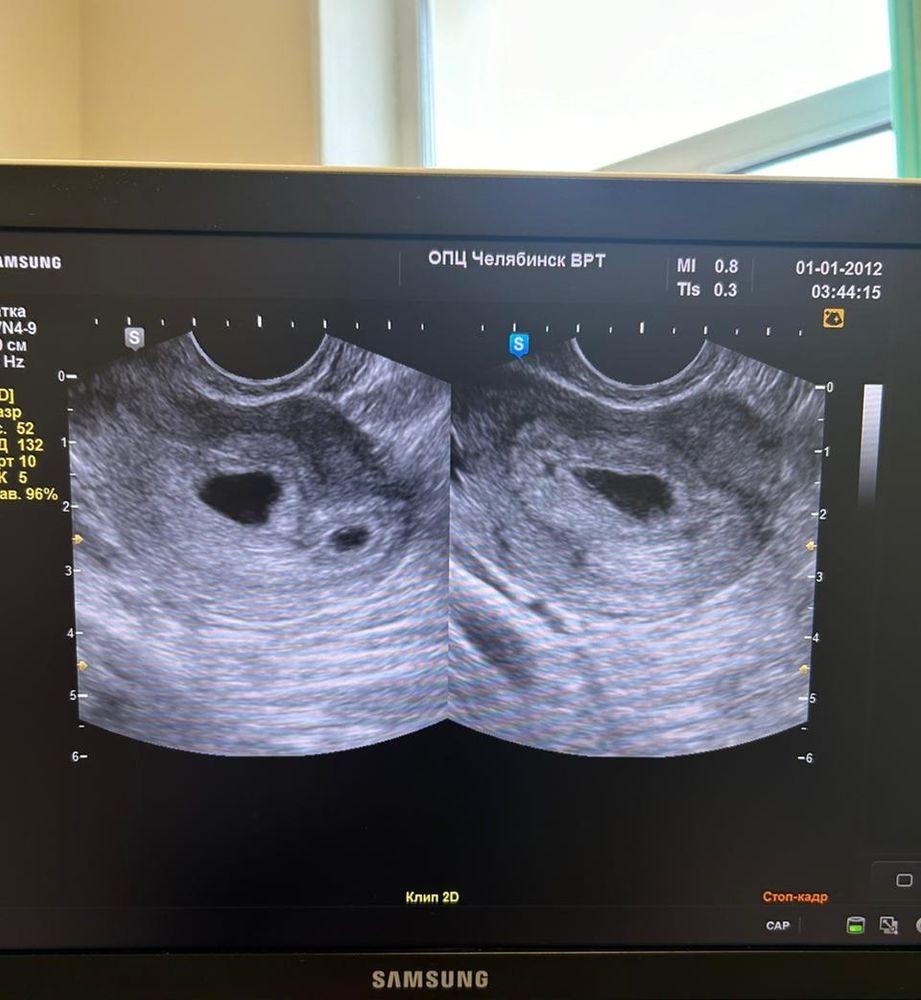

23 дпп узи